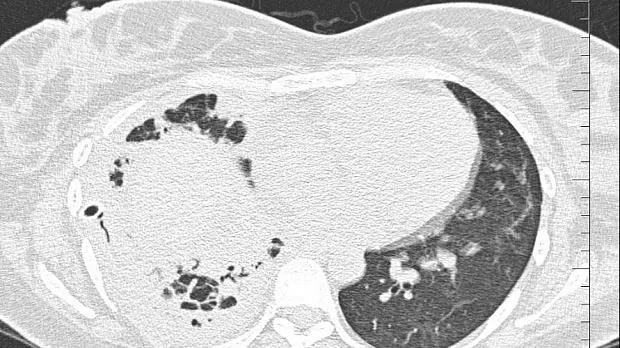

08.06.2020 проведена повторная установка блокатора в промежуточный бронх (блокатор Medlung №13) с хорошим клиническим эффектом (сброс воздуха по плевральному дренажу прекратился через 8 часов после вмешательства). Подтверждено данными Р-КТ органов грудной клетки.